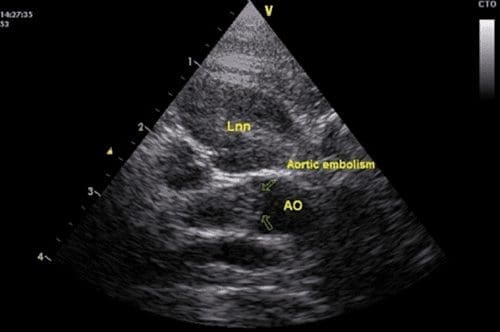

An abdominal ultrasound confirmed the presence of bilateral iliac lymph node enlargement (Approx 1.09 x 1.49cm). FNAs were obtained;. The left and right iliac lymph nodes contained a mixed lymphoid population with frequent plasma cells, eosinophils and macrophages consistent with a reactive change. The caudal pole of the spleen showed some irregularities. The parenchyma here appeared moth-eaten and reticular. Aspirates were obtained and results were consistent with extramedullary haematopoiesis and evidence of inflammation

An aortic embolism was identified at the trifurcation and was occluding the majority of the blood flow to the right iliac artery. Both kidneys had evidence of mild pyelectasia possibly as a result of fluid therapy. The liver was enlarged and hyperechoic which may have been related to endocrine disease. The stomach and intestinal tract were unremarkable. The urinary bladder was small.